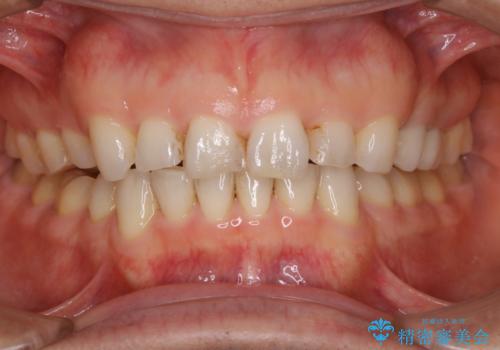

前歯のステイン(着色)をPMTCでキレイに

- コーヒーを普段からよく飲むため、着色・ステインが気になるとのことで来院されました。着色が前歯のみに付着していたためPMTC自費クリーニングの30分コースを行いました。